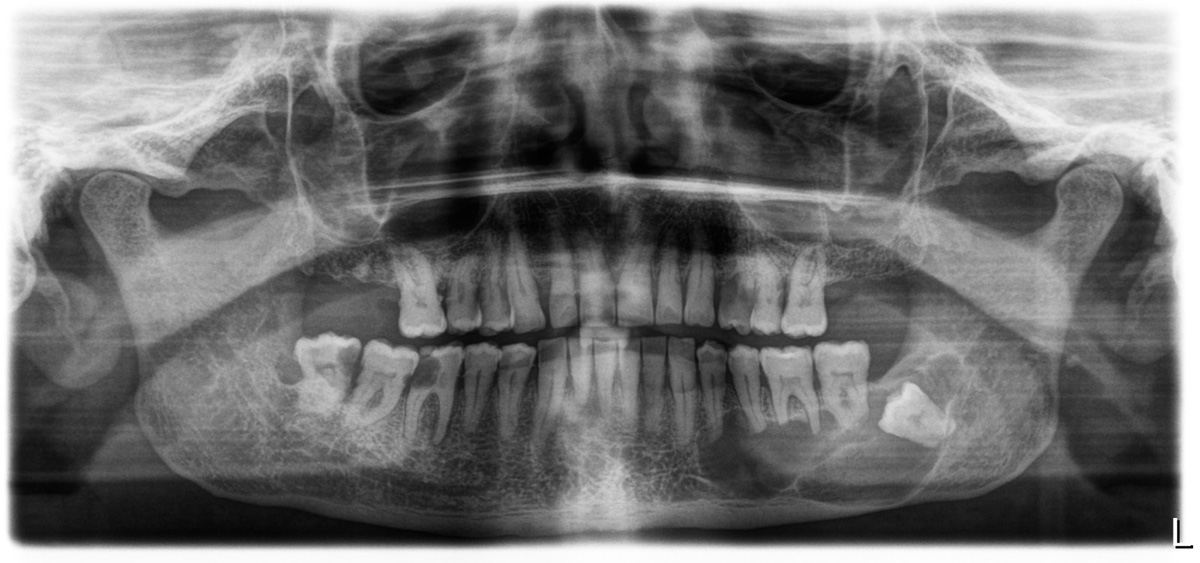

Caso di Cheratocisti in anestesia generale

Caso di Chirurgia Orale